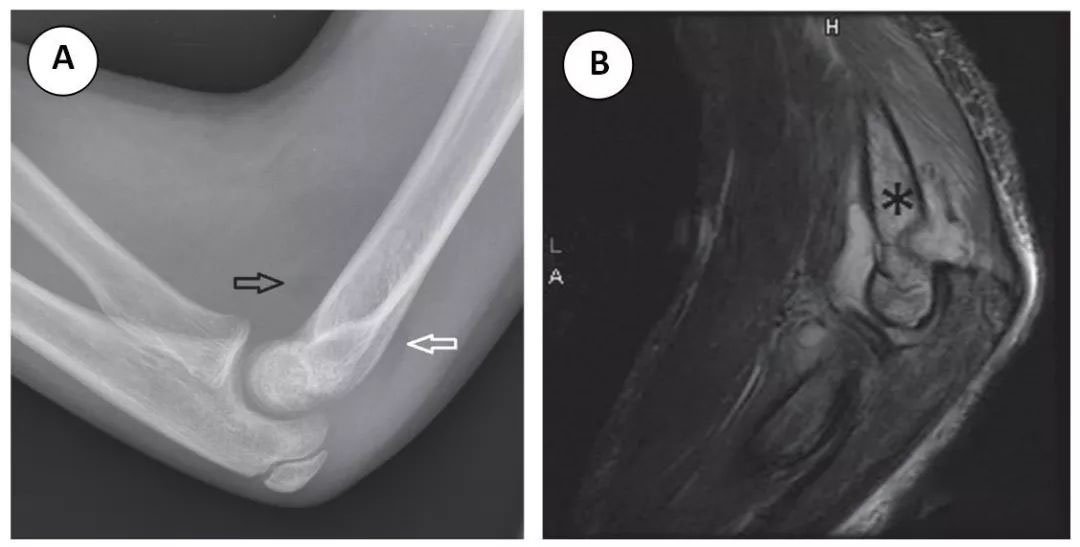

在肘关节侧位片上,当前脂肪垫移位或存在与肱骨远端邻接的后脂肪垫时,提示存在肘关节积液 (图 3A)。在 x 线片上看到肘关节积液而无明显骨折,常提示外伤后的隐匿性骨折 (图 3B)。

图 3 一名 7 岁男童跌倒后持续肘部疼痛。(A) 肘关节侧位片显示前脂肪垫(也称为帆船征)(黑色箭头) 和后脂肪垫 (白色箭头) 移位,提示肘关节中度积液。未见明显骨折线。(B)STIR 序列图像显示肘关节积液。此外,肱骨髁上可见骨髓水肿 (星号)。这些发现与影像学上的隐匿性骨折特征相符。